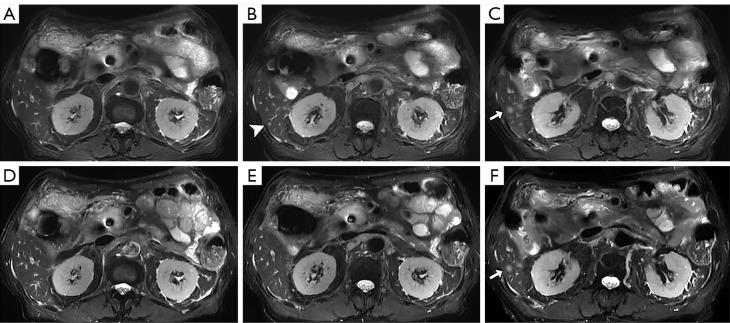

Magnetic resonance imaging (MRI) plays a crucial role in the diagnosis of abdominal conditions. A comprehensive assessment, especially of the liver, requires multi-planar T2-weighted sequences. To mitigate the effect of respiratory motion on image quality, the combination of acquisition and reconstruction with motion suppression (ARMS) and respiratory triggering (RT) is commonly employed. While this method maintains image quality, it does so at the expense of longer acquisition times. We evaluated the effectiveness of free-breathing, artificial intelligence-assisted compressed-sensing respiratory-triggered T2-weighted imaging (ACS-RT T2WI) compared to conventional acquisition and reconstruction with motion-suppression respiratory-triggered T2-weighted imaging (ARMS-RT T2WI) in abdominal MRI, assessing both qualitative and quantitative measures of image quality and lesion detection.

There ACS-RT T2WI protocol had a significantly reduced median scanning time compared to the ARMS-RT T2WI protocol (148.22±38.37 13.86±1.72 seconds). However, ARMS-RT T2WI had a higher PSNR than ACS-RT T2WI (39.87±2.72 38.69±3.00, P<0.05). Of the 201 liver lesions, ARMS-RT T2WI detected 193 (96.0%) and ACS-RT T2WI detected 192 (95.5%) (P=0.787). Of the 97 biliary system lesions, ARMS-RT T2WI detected 92 (94.8%) and ACS-RT T2WI detected 94 (96.9%) (P=0.721). Of the 110 pancreatic lesions, ARMS-RT T2WI detected 102 (92.7%) and ACS-RT T2WI detected 104 (94.5%) (P=0.784). The CR analysis showed the superior performance of ACS-RT T2WI in certain lesion types (hemangioma, 0.58±0.11 0.55±0.12; biliary tumor, 0.47±0.09 0.38±0.09; pancreatic cystic lesions, 0.59±0.12 0.48±0.14; pancreatic cancer, 0.48±0.18 0.43±0.17), but no significant difference was found in others like focal nodular hyperplasia (FNH), hepatapostema, hepatocellular carcinoma (HCC), cholangiocarcinoma, metastatic tumors, and biliary calculus.

ACS-RT T2WI ensures clinical reliability with a substantial scan time reduction (>80%). Despite minor losses in detail and SNR reduction, ACS-RT T2WI does not impair lesion detection, marking its efficacy in abdominal imaging.